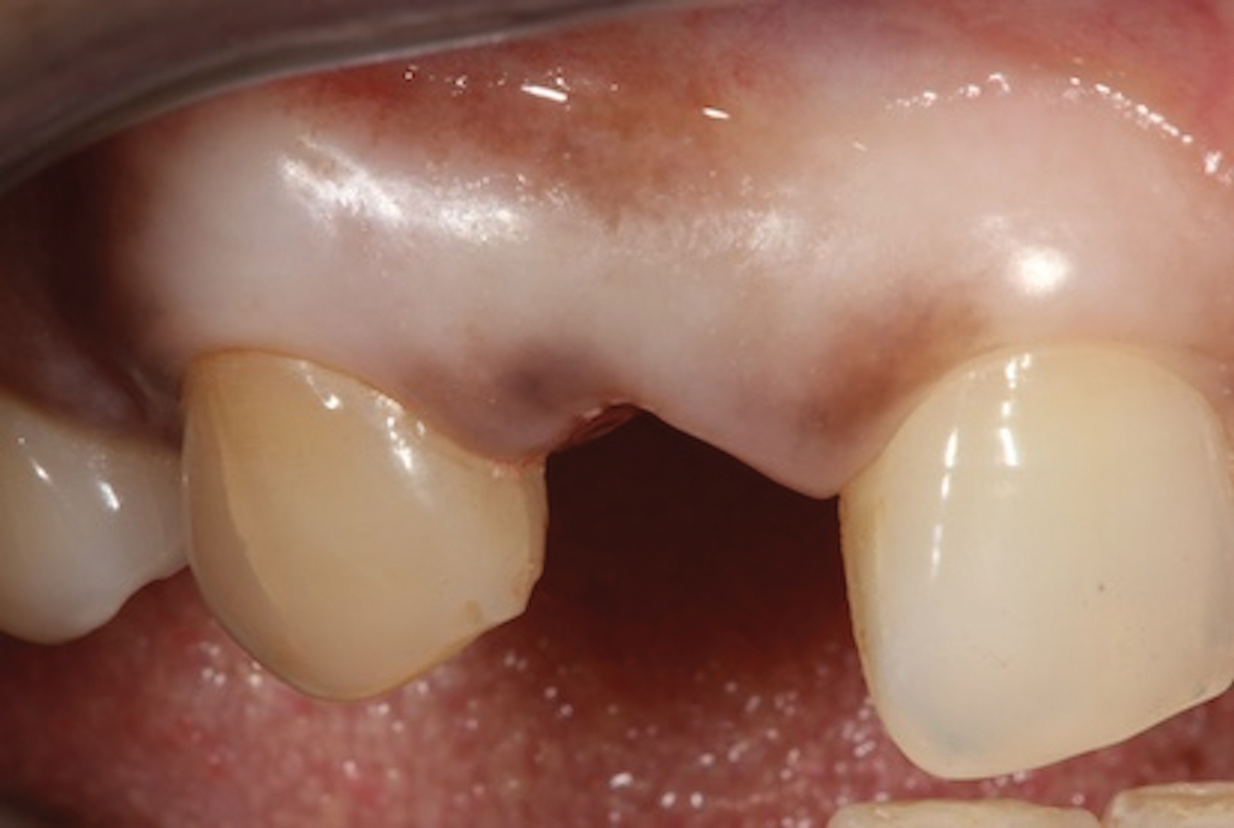

(2.) Close-up right lateral view of the tooth No. 7 site following extraction and implant placement.

Figure 2

Depending on whether patients present with an existing edentulous space or a non-restorable tooth requiring extraction, as well as other factors, their long-term treatment goals may vary. Nonetheless, each case should be evaluated to identify patients' needs regarding immediate restoration. In the example case presented here, a radiographic examination of a discolored canine lead to the discovery of a lateral incisor (tooth No. 7) with internal resorption that required extraction (Figure 1). The tooth was extracted, and an implant was subsequently placed (Figure 2); however, the patient would be unable to complete the treatment for an extended period of time, so a fiber-reinforced composite bridge was chosen to serve as an ideal long-term provisional replacement option.